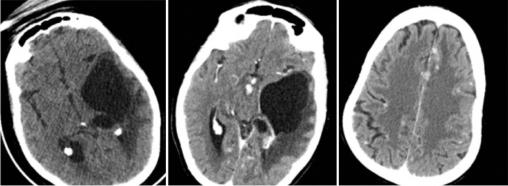

Cette femme de 44 ans avait un tableau d’hypertension intracrânienne et des troubles du comportement, un syndrome pyramidal droit, une paralysie faciale centrale droite, un syndrome confusionnel et un œdème papillaire ; pas de particularité pour le reste de l’examen, notamment pulmonaire. Le bilan biologique (test de sensibilité à la tuberculine, antigène carcinoembyonnaire, métabolisme calcique, cytologie du lavage bronchoalvéolaire) et la radiographie pulmonaire étaient normaux. La tomodensitométrie (TDM) cérébrale (fig. 1 ) montrait une lésion kystique temporale gauche exerçant un effet de masse sur la ligne médiane avec un œdème périlésionnel. Après injection il y avait une prise de contraste micronodulaire leptomeningée diffuse et de la corne occipitale du ventricule latéral gauche. L’imagerie par résonance magnétique (IRM) [fig. 2 ] montrait une volumineuse lésion kystique expansive temporale gauche, dont les parois ne se rehaussaient pas après injection du produit de contraste avec un hypersignal T2 périlésionnel ainsi qu’un engagement temporal. La résection chrirugicale et la corticothérapie permettaient une amélioration neurologique immédiate. L’histologie était en faveur d’un granulome épithéloide gigantocellulaire sans nécrose caséeuse.

La sarcoïdose est une granulomatose systémique de cause inconnue, elle peut atteindre l’ensemble du système nerveux : nerfs crâniens, parenchyme cérébral, leptoméninges et nerfs périphériques. L’atteinte neurologique peut être inaugurale et le diagnostic est alors difficile.1 Six à 30 % des patients ayant une neurosarcoïdose ont une hydrocéphalie soit communicante par altération de la résorption du liquide céphalorachidien (LCR), soit plus fréquemment obstructive du fait d’une infiltration granulomateuse de l’épendyme et des plexus choroïdes. Une forme rare d’hydrocéphalie obstructive est représentée par les trapped ventricular compartements, qui peuvent concerner le 4e ventricule, la corne temporale des ventricules latéraux, prenant le nom d’entrapped temporal horn, elle est la conséquence d’un obstacle à la circulation du LCR au niveau du trigone du ventricule latéral, résultant de l’infiltration granulomateuse de l’épendyme et du plexus choroïde, isolant la corne temporale contenant le plexus choroïde du reste du système ventriculaire. Du fait de la présence du plexus sécrétant du LCR, la cavité s’agrandit progressivement et se comporte comme un processus expansif.